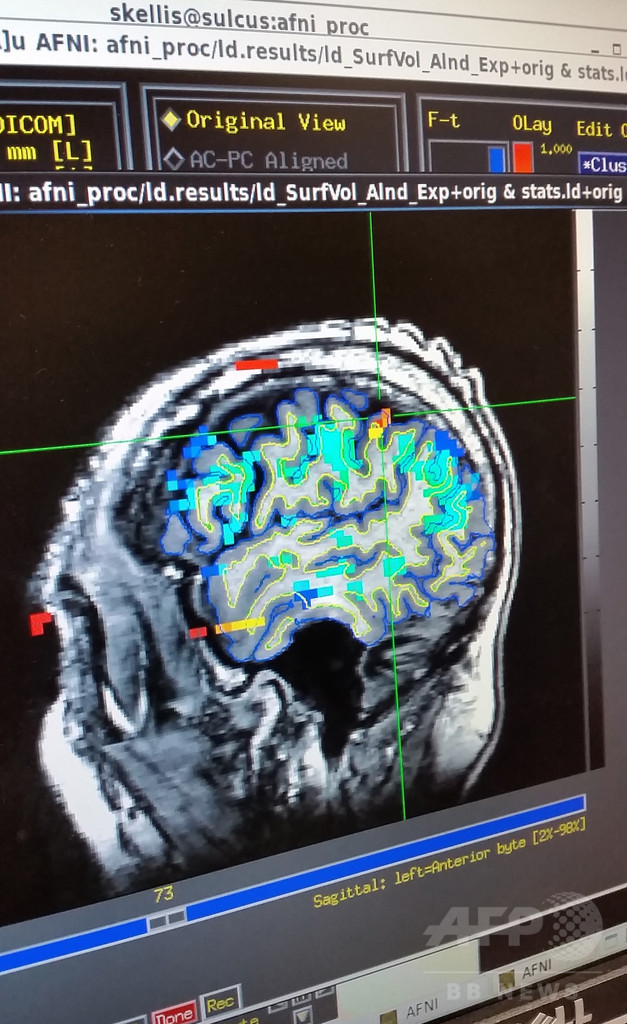

プロテーゼを制御するために脳インプラントを用いるこれまでの試みでは、動作を制御する脳部位の運動皮質に脳インプラントを埋め込んでいた。一方、今回の実験は、2個の微小電極アレイを後頭頂葉(PPC)に埋め込んで実施した。PPCは「手を伸ばす」「つかむ」などの動作をするための意図を処理する脳部位だ。